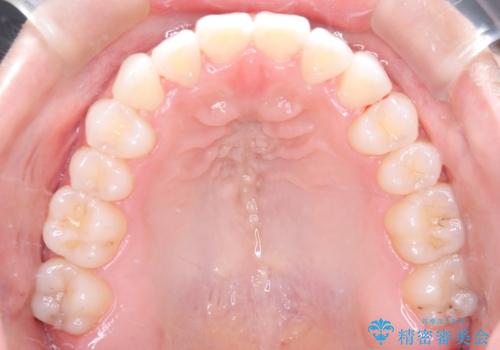

MARPEで非抜歯矯正|オープンバイトと八重歯を改善

- 治療計画

上顎にTAD(矯正用アンカースクリュー)を設置し、MARPEにより骨格レベルで上顎の幅を拡大。数週間の拡大期間を経て十分なスペースを確保したのち、マウスピース型矯正装置(インビザライン)で歯列全体を整えました。八重歯もアーチ内に自然に収まり、非抜歯で審美性と機能性を両立。治療後は「噛み合わせが安定して笑顔に自信が持てるようになった」とご本人にも大変満足していただきました。